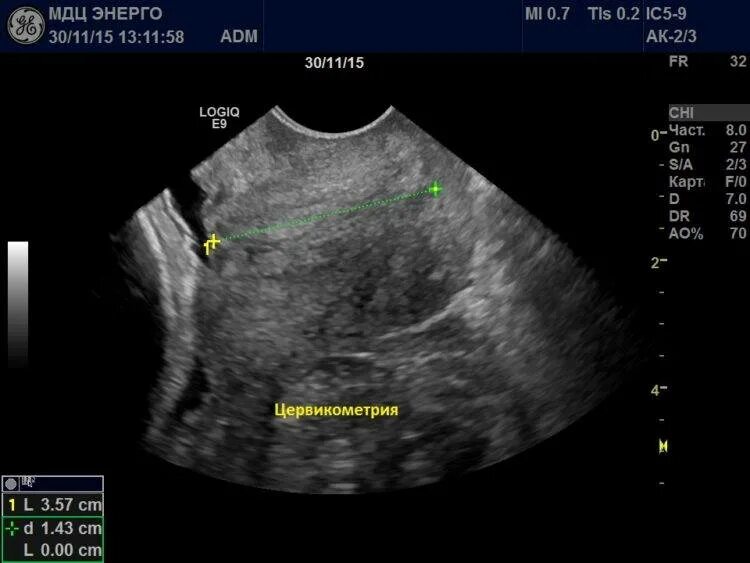

Цервикометрия при беременности как делают